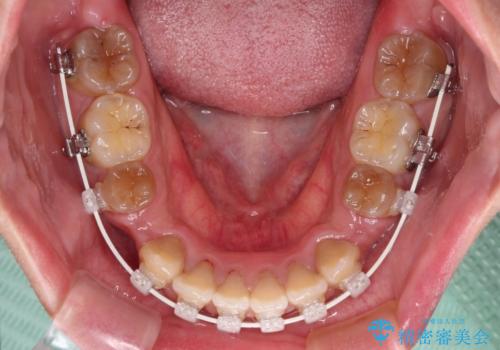

- 矯正装置

- 審美装置

- 治療期間

- 2年6ヶ月

- 治療回数

- 10-30回